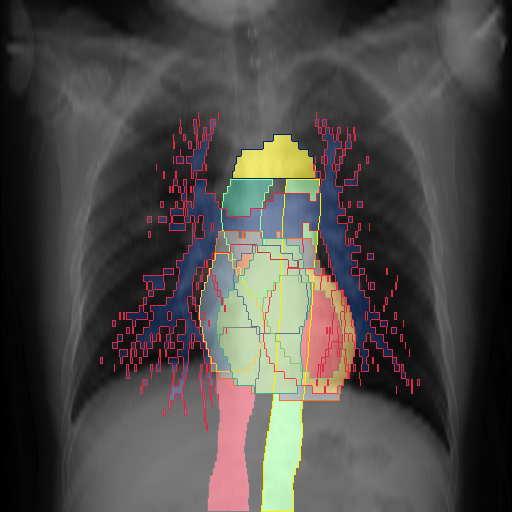

We show qualitative results for frontal projections in Fig. 2. We show a subset of classes belonging to the supercategories lungs, vascular systems, bones, and abdomen/digestive system. The predictions show minor deviations at the boundaries of the individual classes of the respiratory and vasculature system, while some inaccuracies become visible in the abdominal area. The qualitative results for the lateral projections are displayed in Fig. 2. Akin to the frontal view, the predictions show smoother borders but align with the ground truth. Apart from this, the segmentations provide matching insights on the thoracic anatomy with a slight deviation from the ground truth for both frontal and lateral views.

We display qualitative results in Fig. 3. The annotators tend to be content with most annotations. There are edits at the extensions of the esophagus, trachea, and aorta and corrections of the lower ribs. There is little consensus for classes in the abdominal area, such as the stomach, as seen on the right of Fig. 3 . In contrast, the annotators often align for bone classes.